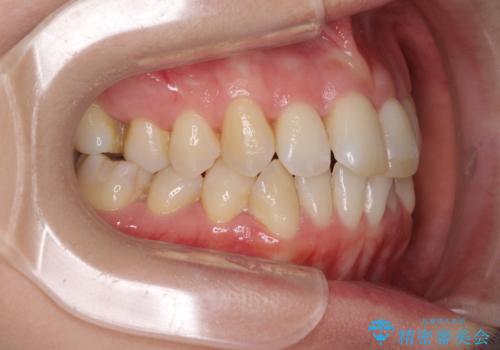

- 奥歯の咬み合わせを気にして来院された患者様です。

上顎骨の幅が下顎骨よりも小さいので、拡大装置により骨幅を広げて上下関係を改善し、その後インビザラインにて歯並びを整えることとしました。

上下の骨幅を改善したことで、スムーズに歯列矯正を行うことができました。

奥歯の咬み合わせを改善する必要があったため、治療は長期化しましたが、きっちりと仕上げることができました。